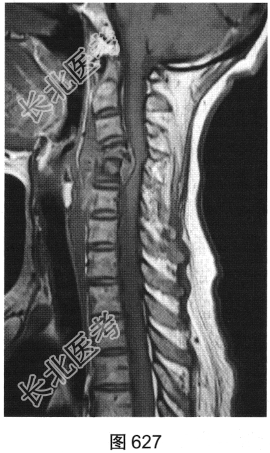

- [材料题] 患者男性,34岁,近数月乏力,偶有低热。颈部疼痛2个月余,逐渐加重,有轻压痛,颈部活动受限。

- 多项选择题2.[提示]患者行颈椎X线、CT和MRI检查,见图623~图628。首先应考虑患者为下列哪种疾病( )